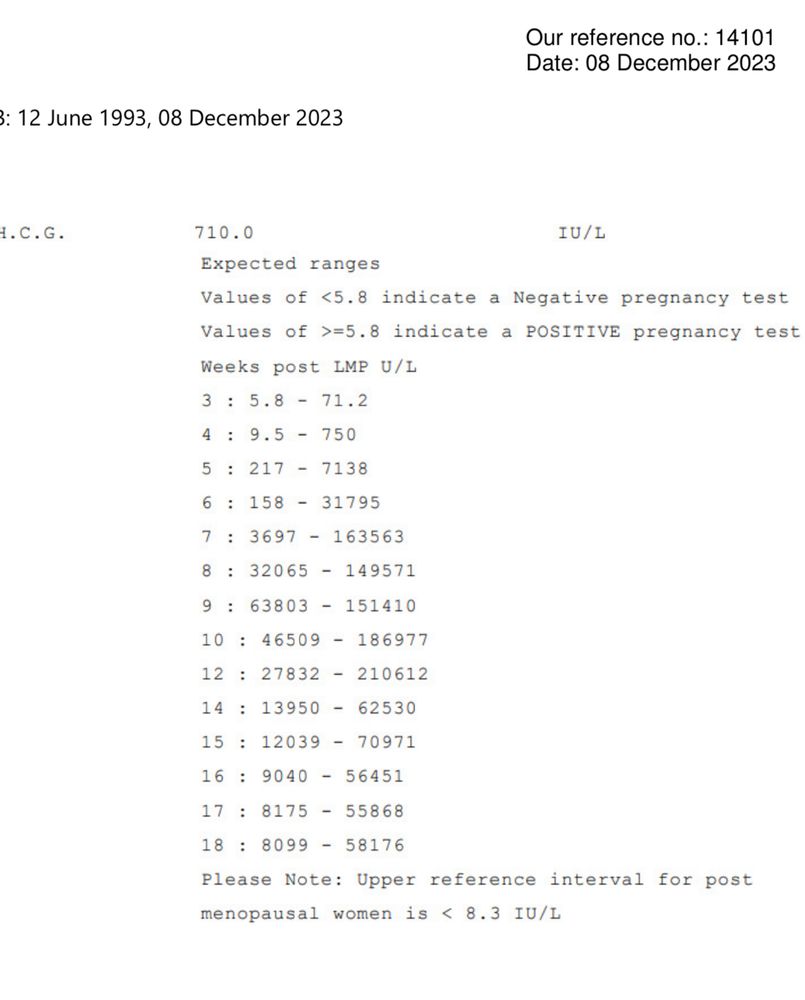

Здравствуйте девочки - вопрос возможно глупый но ситуация странная. Итак, в прошлую субботу мне исполнилось 3 недели после 5-дневного переноса эмбрионов. Итак, сканирование показало эмбрион размером 1,9 мм и плодное яйцо диаметром 9,5 мм. Я сдавала ХГЧ 4 раза за этот период и все в порядке. Вчера сделала сканирование (то есть через 4 недели после переноса) и уже виден только мешок 15,3 мм, а эмбрион исчез? Может ли быть такое - одну неделю эмбрион существует, а вторую неделю чудесным образом исчезает? У меня не было ни кровотечения, ни болей в животе. Прикрепляю фото первого скана с эмбрионом и второго вчерашнего скана без эмбриона. Врач рекомендовал мне продолжить лечение до следующего четверга и сделать еще одно сканирование через 5 недель после переноса. Любые предложения и советы будут оценены по достоинству. Большое спасибо

это и скан и анализ крови в один день

это и скан и анализ крови в один день